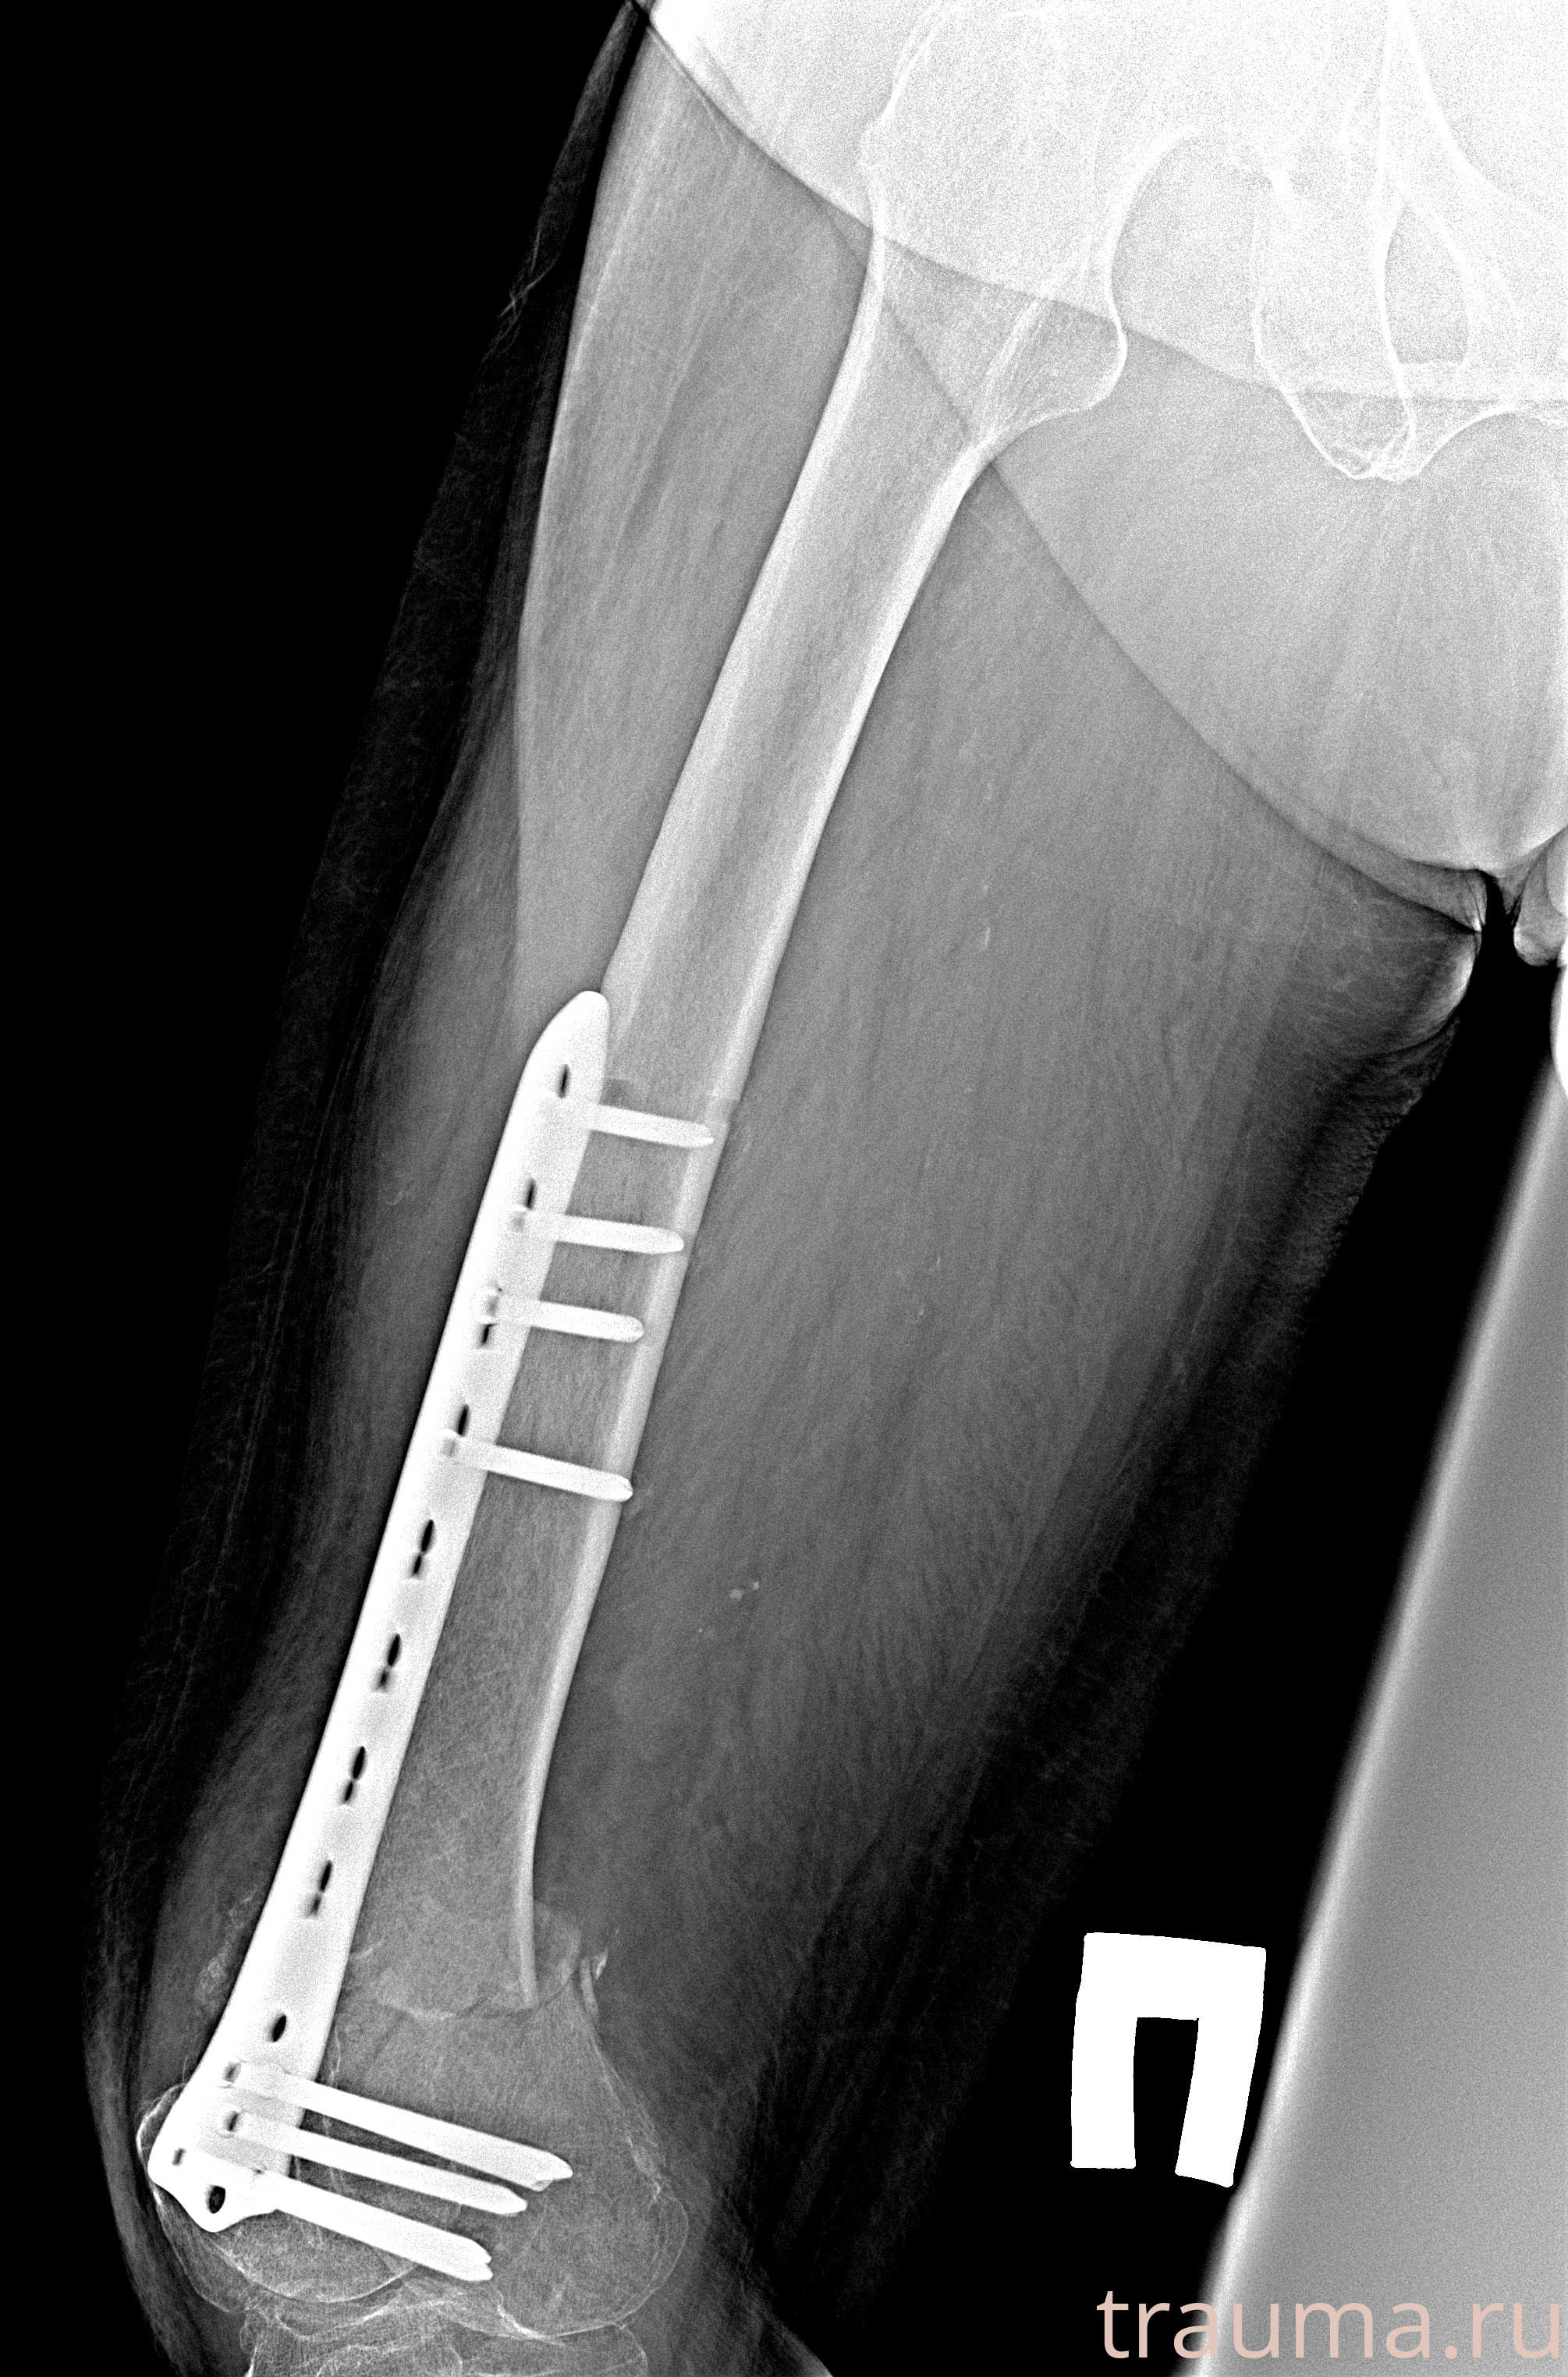

Рентгенограммы

Рентген на дому: по вашему адресу приезжает врач-рентгенолог, травматолог-ортопед с мобильным рентгеновским аппаратом, проводит диагностику травмы или заболевания, делает необходимые рентгенограммы, дает рекомендации по дальнейшему лечению. Получить качественные снимки в домашних условиях возможно благодаря уникальной методике, разработанной МосРентген Центром для института  Склифосовского